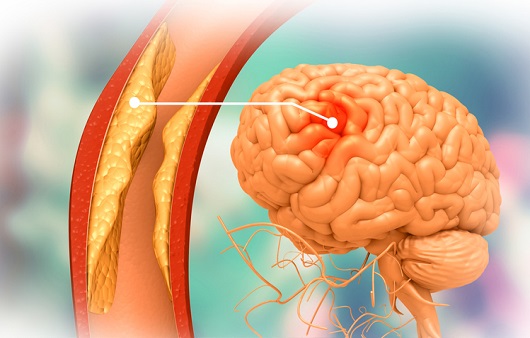

뇌경색은 뇌혈관이 막혀서 뇌의 일부가 손상되는 질환으로 동맥경화증에 의해 병든 혈관에서 발생하는 혈전이 심장이나 굶은 뇌동맥 등에서 떨어져 나와 말단부 뇌혈관을 막아 뇌손상을 일으킬 수 있답니다.